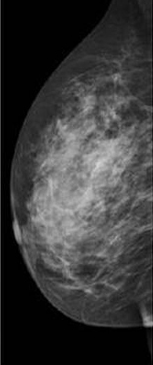

Los quistes son lesiones benignas de mama de contenido líquido. Suelen aparecer en contexto de una mastopatía fibroquística que es la lesión benigna de la mama más frecuente. Es una alteración funcional, en relación con los cambios hormonales y suele cursar con dolor y tensión mamaria, fundamentalmente en los cuadrantes supero-externos. El diagnóstico se confirma mediante pruebas de imagen, donde en la ecografía se diferencian los nódulos sólidos de los líquidos o quísticos y permite medirlos mejor. En la mamografía se visualizan las zonas de mayor fibrosis. El tratamiento suele ser médico, con fármacos, además de beneficiarse de cambios en la dieta como reducir el consumo de cafeína y grasas.

– El diagnóstico clínico de sospecha de estas lesiones benignas de mama suele confirmarse mediante pruebas de imagen (mamografía y/o ecografía), y a veces es preciso completarlo con biopsia.